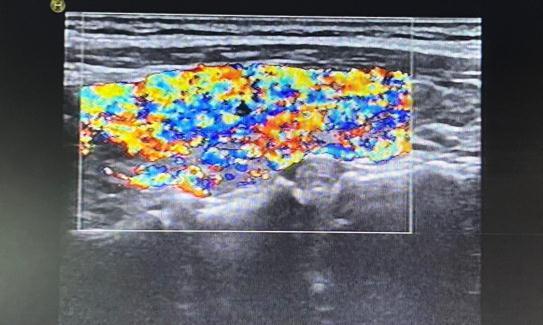

毒性弥漫性甲状腺肿(Graves病):大多为均匀性肿大,也有表现为非均匀性肿大的(较少),通常表现为腺体弥漫性低回声。很多患者就因为发现脖子肿大来就诊。毒性弥漫性甲状腺肿最典型的超声表现为“火海征”,即甲状腺的血供异常丰富,甲状腺上动脉通常都有增宽,一般超过2mm,流速增快。

图片